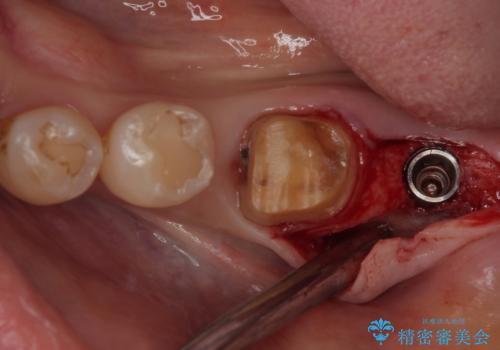

- 左下奥のクラウンに違和感を感じるとのことで来院された患者様です。

最後方歯は歯槽骨よりも深い部分にまでむし歯が及んでおり、患者様と相談の上、インプラントによる補綴治療を行うこととしました。

根尖部の病変が小さいことから抜歯即時埋入が選択されるところですが、抜歯窩洞が大きくなることと、窩洞直下に神経や血管が走行していることから、抜歯してから2,3ヶ月待機してから埋入することとしました。

骨の高さが不十分であったため、インプラント強度を維持しながらも高さの小さいインプランを使用しました。